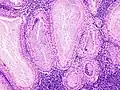

The appearance of this tumor under the microscope is unique. There are cystic spaces surrounded by two uniform rows of oncocytes, which are epithelial cells with abundant, granular, eosinophilic cytoplasm.[7] The cystic spaces have epithelium referred to as papillary infoldings that protrude into them. Additionally, the epithelium has lymphoid stroma with germinal center formation.

Histopathology of Warthin tumor in the parotid gland. Another view of a file "Warthin tumor (1).jpg". H&E stain.

Histopathology of Warthin tumor in the parotid gland. Higher magnification of a file "Warthin tumor (1).jpg". H&E stain.

Intermediate magnification micrograph of a Warthin tumor.